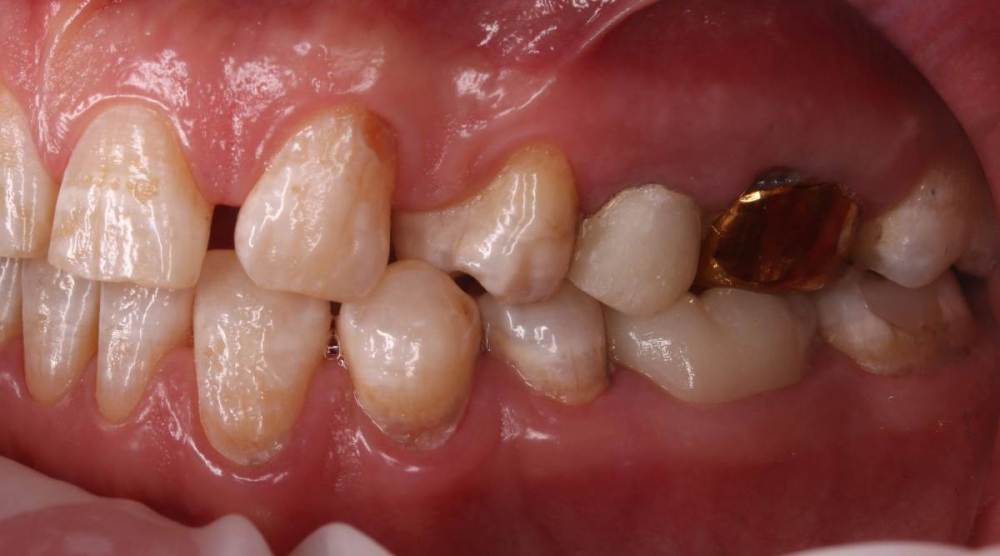

Роман1982 Опубликовано 25 мая, 2021 Поделиться Опубликовано 25 мая, 2021 Добрый день! Очень хотелось бы услышать объективное мнение специалистов. 40 лет На верхней челюсти от рождения не хватает двух резцов (12 и22) Перекрестный прикус В принципе, особо не беспокоит, хотя есть щелчки в суставе слева, если широко открывать челюсть. Из-за неправильно проводимого ранее лечения, встал вопрос об удалении в ближайшее время 25 и 26 зуба сверху и 46 снизу (на фото обведены красным). Ортопед рекомендовал пройти ортодонтическое лечение, т.к. в противном случае в дальнейшем могут возникнуть сложности с имплантами и коронками, может ухудшиться ситуация с суставом. Вот пытаюсь взвесить все за и против. Понимаю, что прикус было бы желательно исправить. Но! При текущем состоянии зубов не навредит ли это им еще больше? Исправление прикуса повлечет за собой необходимость установки на верхней челюсти еще двух дополнительных имплантов (на месте отсутствующих12 и 22). После исправления прикуса велика вероятность тотального протезирования. По словам того же ортопеда, может не хватить высоты сустава и тогда на все зубы понадобиться устанавливать коронки. Стоит ли затевать ортодонтическое лечение в данной ситуации или лучше не трогать то, что как-то функционировало 40 лет? Хотелось бы услышать аргументирование мнение. Ссылка на комментарий